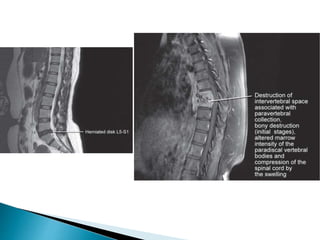

• 30.

 Shoulder – ◦Rotator cuff tear ◦ Impingement syndromes ◦ Instability ◦ Osteonecrosis ◦ Pathological conditions of the tendon  Spine – ◦ Evaluation of intervertebral disk disease ◦ Discitis ◦ Pyogenic and tuberculous infections